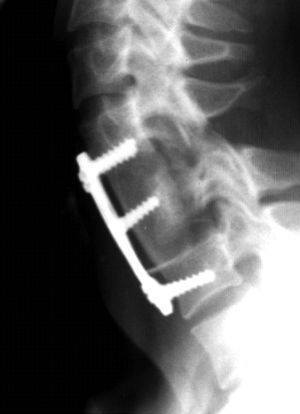

Вместо тела позвонка устанавливается шейный кейдж или сетчатый имплант (mesh) или же фрагмент подвздошной кости пациента. Далее, указанная конструкция фиксируется шейной пластиной. Т.о. спинной мозг освобождается от компрессии и создаются условия для его восстановления. (Рис.8)